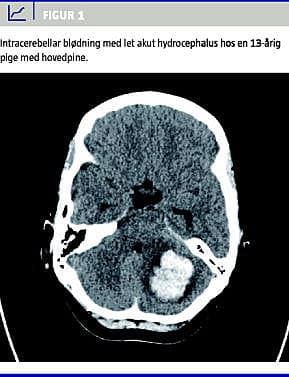

En 13-årig, tidligere sund og rask pige blev indlagt akut pga. hovedpine. Hun var vågnet med let hovedpine, som var blevet forværret i løbet af dagen. Hun havde i ugerne op til denne sygdomsepisode været plaget af hovedpine i perioder. Ved ankomsten var pigens luftveje, vejrtrækning og cirkulation stabil, Glascow Coma Scale (GCS) var på 14, hun var let hypoterm med temperatur på 35,4 °C målt rektalt. Hun fremstod lettere bevidsthedspåvirket, men kunne dog nemt vækkes og svarede helt relevant. Ved neurologisk og somatisk undersøgelse fandt man intet unormalt. Blodprøverne viste normale forhold, inkl. koagulationstal, og der var normal puls og normalt blodtryk. Pga. lettere bevisthedspåvirkning i forbindelse med hovedpinen foretog man en akut computertomografi (CT) af cerebrum. Tomografien afslørede en 5 × 3,5 cm stor cerebellar blødning i venstre hemisfære og akut hydrocephalus (Figur 1 ).